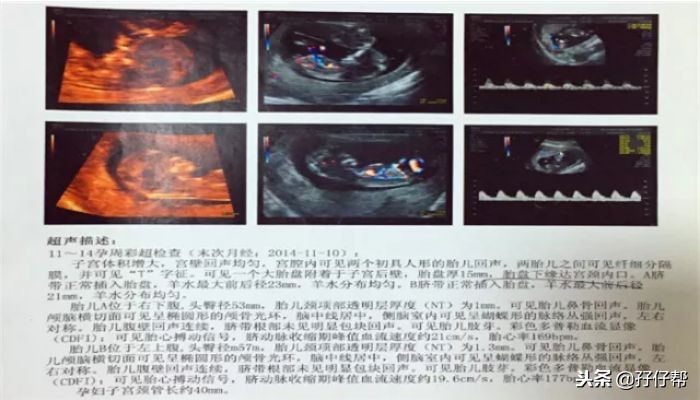

据之前了解的信息,单绒双羊可是TTTs的重灾区啊!我的NT报告单如下图(1)⏬⏬

下图(2)⏬⏬

NT 结果挺好的,只是有一个宝宝胎心偏快,177次/分。胎盘目前处于前置状态,两胎宝宝孕周相差两天。

综合所有产检结果,医生评估了我的孕育情况:目前的妊娠状态良好,暂无异常,B超确诊我是单绒毛膜双羊膜囊双胎妊娠,两胎儿共用一个胎盘,是同卵双胎中最常见的一种,风险系数仅次于单绒单羊妊娠。